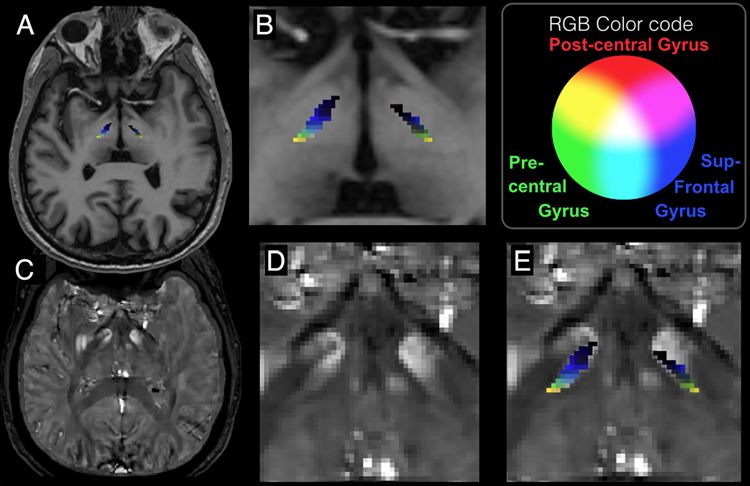

研究结果显示,对于丘脑、运动前区、运动区和感觉区,STN连接与QSM值强度呈强负相关;而对于额叶、壳核和脑干,STN连接与QSM值强度呈强正相关(图1)。

图1. 3个感兴趣区的三原色(RGB)叠加示图,其中红色、绿色和蓝色分别代表中央后回、中央前回和额上回。A为T1加权图像上显示RGB叠加;B为A的放大图;C为水平位重建的QSM图像;D为C图的放大;E显示RGB叠加的STN。